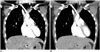

Using contrast-enhanced dual energy CT data in all body regions, iodine map specifically shows iodine distribution in tissues with improved iodine contrast-to-noise ratio, but the bone and calcium are also included in the map (Figs. 8, 9). In the thoracic region, dual-energy lung parenchymal iodine or pulmonary blood volume (PBV) map, as a surrogate of lung perfusion, is mainly used to improve the diagnosis of pulmonary thromboembolism. By this method, characteristically wedge-shaped iodine-deficient lung lesions are detected, which are not apparent on conventional pulmonary CT angiography (Fig. 7) (26, 27, 28). In pulmonary thromboembolism, dual-phase dual-energy PBV map can be used to differentiate between acute and chronic phases by identifying delayed systemic collateral flow at the expense of higher radiation dose (29). Dual-energy PBV map can demonstrate that endothelial dysfunction represented with hypoxic peripheral arteriolar vasoconstriction is reversible after administration of oral sildenafil, supported by reduced PBV coefficients of variation due to lung perfusion heterogeneity, in smoking-associated emphysema (30).

|

In all body regions, due to improved lesion-to-background contrast, enhancing lesions or vessels are more conspicuous on the iodine map (Fig. 8). Iodine map is helpful not only to distinguish a particularly hyperdense, cystic lesion or hematoma from enhancing lesion, but also to clearly delineate the extent of bowel ischemia (14, 18, 25); in addition, malignant tumors may be more accurately differentiated from benign tumors based on the degree of iodine enhancement (19). Treatment response may be assessed quantitatively by measuring the iodine concentration in enhancing tumors in oncologic patients (14, 18, 28, 31).

In the cardiovascular region, static dual-energy stress myocardial perfusion CT is more useful than coronary CT angiography for the detection of hemodynamically significant coronary artery stenosis by providing myocardial iodine distribution during the early arterial phase (25, 34). In cardioembolic stroke, dual-energy cardiac CT with dual-phase (arterial and 3 minutes delayed) intravenous injection of contrast agent can be used to accurately differentiate between left atrial appendage thrombi and circulatory stasis (35). Iodine map increases confidence in detecting endoleaks after aortic stent graft placement (36).